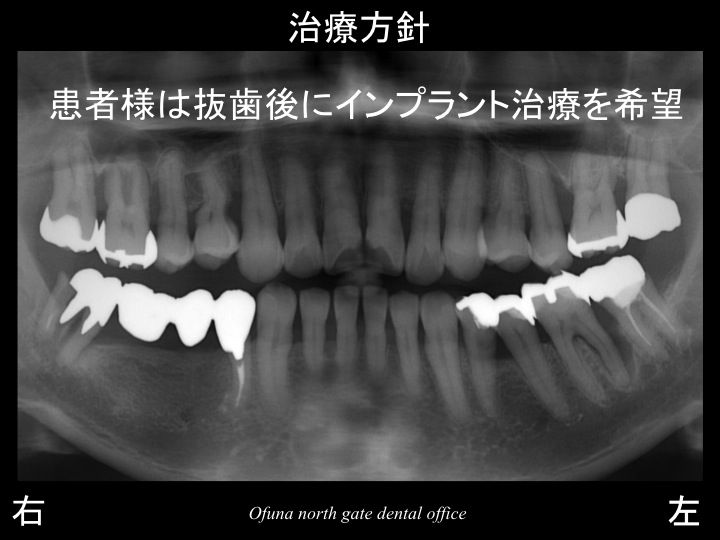

患者様は 抜歯に同意し、抜歯後にはインプラント治療をご希望されました。

もともと歯が2歯部欠損していたわけですから

今回の1歯を抜歯すると

合計3歯分が欠損になります。